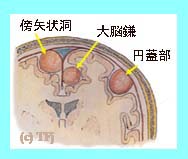

����̐}�͔]�̍��Ƃ̈ʒu�W�A

����̐}�͔]�̍��Ƃ̈ʒu�W�A

���̐}�͔]�̕\�ʂ̖��i�d���j�@

�Ƃ̈ʒu�W�̐}�ł��B

����̐}�͔]�̍��Ƃ̈ʒu�W�A

����̐}�͔]�̍��Ƃ̈ʒu�W�A